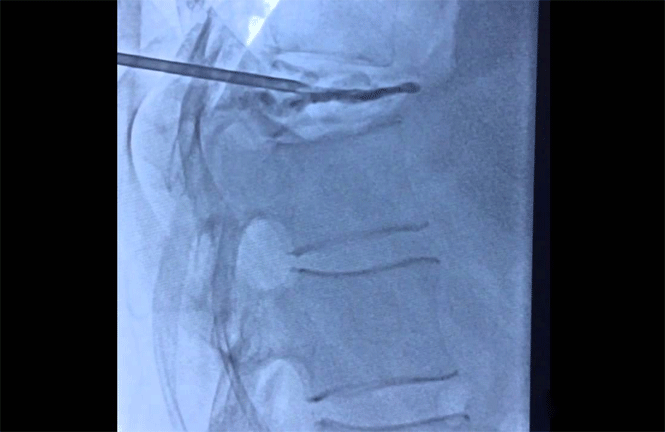

This outpatient procedure involves injecting polymethylmethacrylate (PMMA) into the fractured vertebral bone under radioscopic (X-Ray) guidance. This repairs the fracture and provides relief from pain. The skin surrounding the injection site is numbed with a local anesthetic before the injection begins.